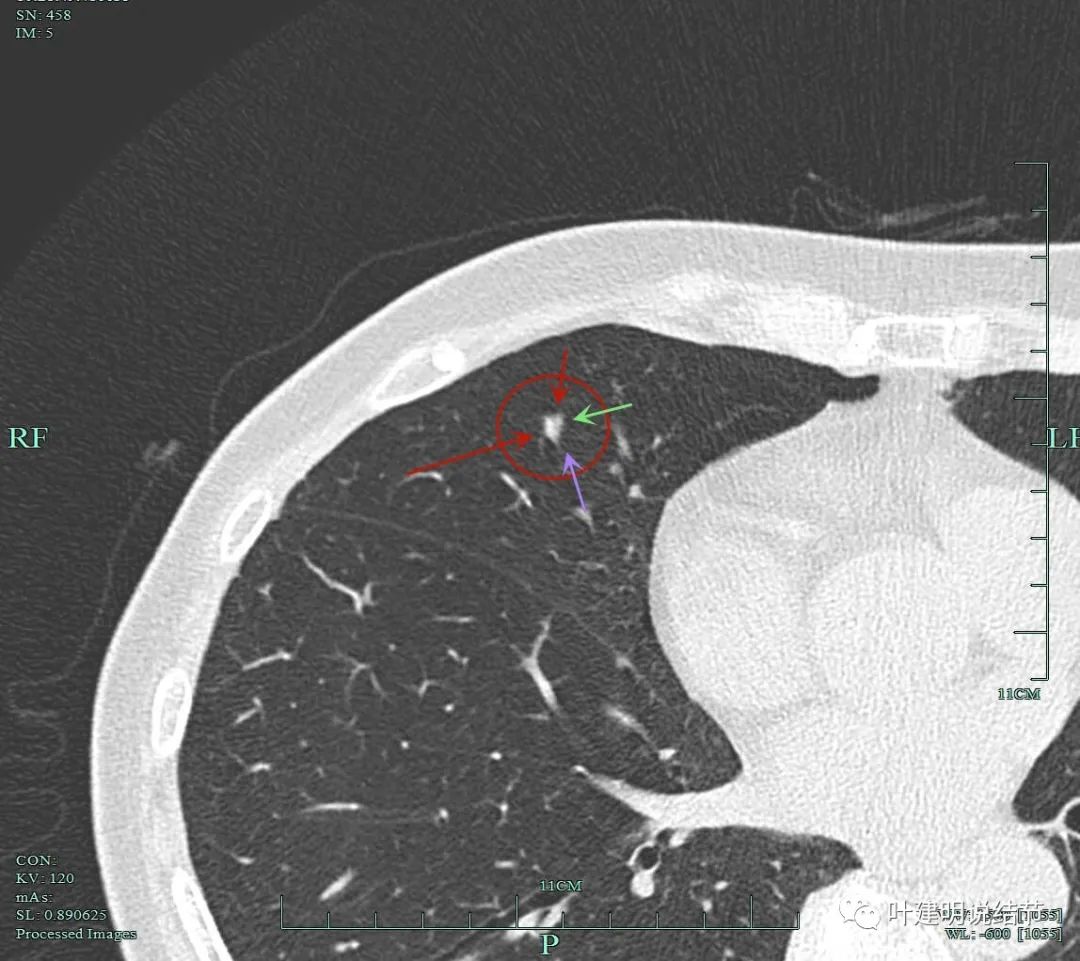

我们手术前做了靶扫描的重建,但当时请影像做的是病灶2、病灶6和病灶8。我的纠结在于中叶这个实性病灶是什么?如果它是炎性的或肺内淋巴结,密度是不是要更高一点?两肺这么多结节都考虑肿瘤范畴,只有这处是炎性或良性的,好像说不大通。我们以前也一直强调:如果多发结节,有的良恶性难定,有的较为明确是恶性,那么难定的也很可能同样的恶性的;有的较为明确是炎性的,那么难定的这处也可能是炎性的,因为致病的因素是一样的。有了这个念头之后,再回头去看中叶的结节,怎么总觉得虽像实性,但不够密实。所以我打电话请影像科同事重新为她中叶这颗也靶重建一下看看细节信息。

病灶9的重建发现不是实性结节,而混合磨玻璃密度。绿色箭头示边上有磨玻璃成分,而且紫色箭头示边缘是毛糙的,红色箭头示整体轮廓是清的。

上图也显示病灶边缘毛糙,不光滑,与胶原结节、淋巴结等良性结节是不符合的。

影像再判断:

右肺中叶病灶9考虑是浸润性腺癌,比其他病灶风险都高,它应该是主病灶了。但鉴于两肺多发病灶基本上都考虑肿瘤范畴的,即使此灶考虑浸润性,但毕竟还小,也有磨玻璃成分,存在转移的概率极小,仍应该可以考虑妥协性的楔形切除。